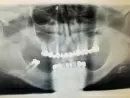

На панорамном снимке в пазухе носа обнаружен пломбировочный материал

При посещении стоматолога был сделан панорамный снимок, обнаружено инороднее тело, предположительно пломбировочный материал. Консультировалась с отоларингологом. Сделала МСКТ. Описание: Костные структуры придаточных пазух носа выражены обычно, без деструктивных или травматических изменений. Верхнечелюстные пазухи симметричные, развиты достаточно, обычной формы и размеров. Слизистая ограниченно утолщена справа, до 2-3 мм, дополнительных образований не выявлено, уровней жидкости не определяется. Ячейки решетчатой кости развиты обычно. Стенки не деформированы. Слизистая не утолщена, ячейки обычной воздушности, дополнительных образований не выявлено. В средней ячейке пазухи справа пломбировочный материал плотностью около 7000 Н, размерами около 5х2х3 мм. Содержимого в ячейках не определяется. Пневматизация клиновидных пазух 2-3 степени. Слизистая не утолщена, пазуха обычной воздушности, дополнительных образований не выявлено. Уровней жидкости не определяется. Лобные пазухи не развиты. Носовые ходы проходимы. Носовая перегородка С-образно искривлена вправо до 3 мм, с наличием гребня на уровне среднего носового хода, до 5,5 мм. Полость носоглотки не сужена, симметрична, дополнительные образования не выявляются.

Заключение: Пломбировочный материал решетчатой пазухи справа. Ограниченное утолщение слизистой правой верхнечелюстной пазухи. Искривление носовой перегородки, с гребнем в области среднего носового хода. Рекомендации: Консультация ЛОР врача.

Предполагали делать операцию по удалению. Заведующий отделением клиники на консультации сказал, что похоже это костная ткань (по плотности). На операцию не направили. Сказал, потому что мы там его не найдем. Боли в правой стороне носа (в глубине) беспокоят, отеки под глазами. Боли носят разный характер: тянущая (от переносицы, отдает в верхние зубы), сильная, пульсирующа я. Я думала, что это гайморит меня беспокоит. Был гайморит двусторонний. Боли беспокоили еще до того, как я узнала об инородном теле.